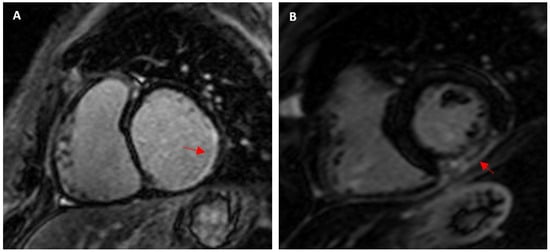

- Cummings, K.W.; Bhalla, S.; Javidan-Nejad, C.; Bierhals, A.J.; Gutierrez, F.R.; Woodard, P.K. A pattern-based approach to assessment of delayed enhancement in nonischemic cardiomyopathy at MR imaging. Radiographics 2009, 29, 89–103. [Google Scholar] [CrossRef] [PubMed]

- Zorzi, A.; Marra, M.P.; Rigato, I.; De Lazzari, M.; Susana, A.; Niero, A.; Pilichou, K.; Migliore, F.; Rizzo, S.; Giorgi, B.; et al. Nonischemic Left Ventricular Scar as a Substrate of Life-Threatening Ventricular Arrhythmias and Sudden Cardiac Death in Competitive Athletes. Circ. Arrhythmia Electrophysiol. 2016, 9, e004229. [Google Scholar] [CrossRef]

- Schnell, F.; Claessen, G.; La Gerche, A.; Bogaert, J.; Lentz, P.-A.; Claus, P.; Mabo, P.; Carré, F.; Heidbuchel, H. Subepicardial delayed gadolinium enhancement in asymptomatic athletes: Let sleeping dogs lie? Br. J. Sports Med. 2016, 50, 111–117. [Google Scholar] [CrossRef]

| Wilson et al. (2011) [20] 1.5 T | 29 12 lifelong veteran endurance and 17 young endurance: marathon, ultramarathon, ironman, triathlon | Veteran: 43 ± 6 y of competitive training Young: 18 ± 7 y of competitive training | 57 ± 6 31 ± 5 | M: 100 1.96 ± 0.14 2 ± 0.14 | Veteran: 6/12 (50%) Young: 0/17 Total: 6/29 (20.7%) | 1 CAD pattern: subendocardial septal and lateral wall infarction pattern 5 non-CAD pattern: 1 subepicardial lateral wall (myocarditis), 4 junctional: basal and mid insertion point, inferior insertion point and mid/apical, inferior mid/apical insertion point, inferior insertion point | - | - |

| Tahir et al. (2018) [11] 1.5 T | 83 Triathletes | 12.6 y competitions, >10 h/wk training | 43 ± 10 | M: 65 1.98 ± 0.12 F: 35 1.73 ± 0.12 | M: 9/54 (16.7%) F: 0/29 Total: 9/83 (10.8%) | Nonischaemic: 5: subepicardial (myocarditis)–inferolateral LV wall, 2: posterior RV insertion points, 1: transmural | M: 990 ± 28 F: 1015 ± 25 M: LGE+ 1005 ± 32 M: LGE- 987 ± 27 | M: 24.8 ± 2.2 F: 27.8 ± 1.9 M: LGE+ 26.3 ± 1.8 M: LGE- 24.4 ± 2.2 |